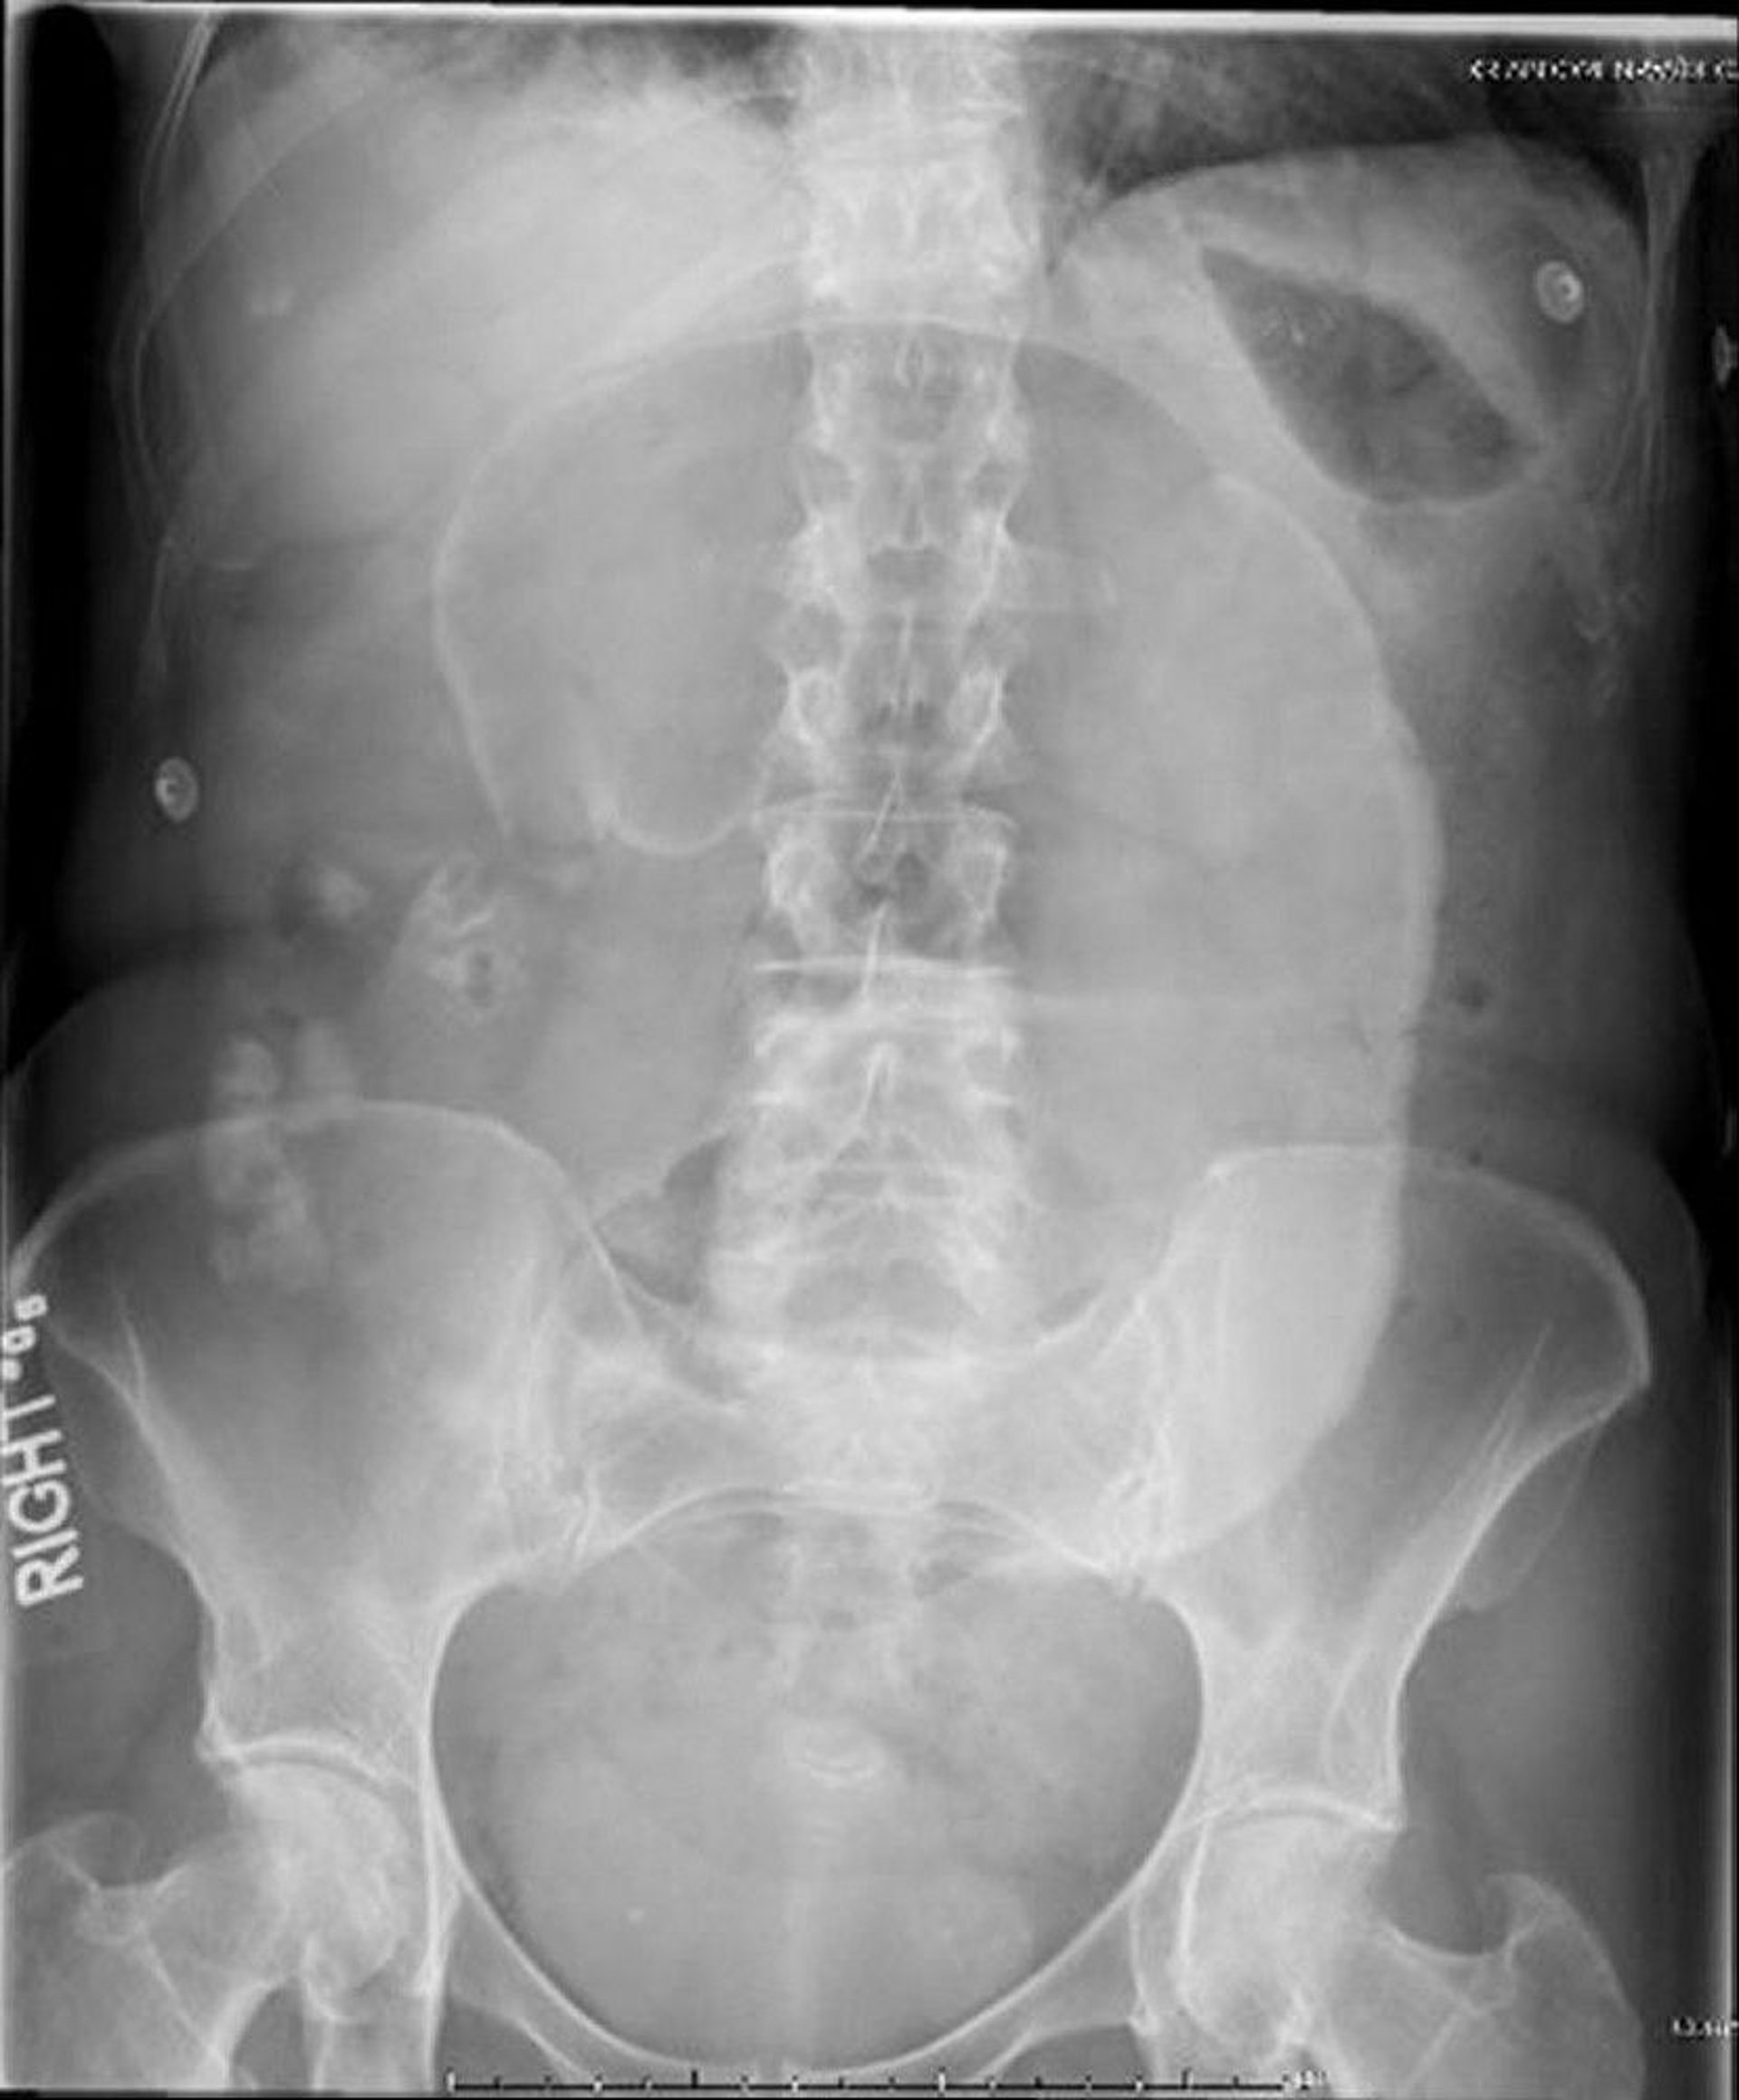

Cecal Volvulus (Abdominal Radiograph)

In this abdominal radiograph, the cecum has twisted around its mesentery, causing a dilated "coffee bean" to project toward the left upper quadrant.

Image provided by Parswa Ansari, MD.